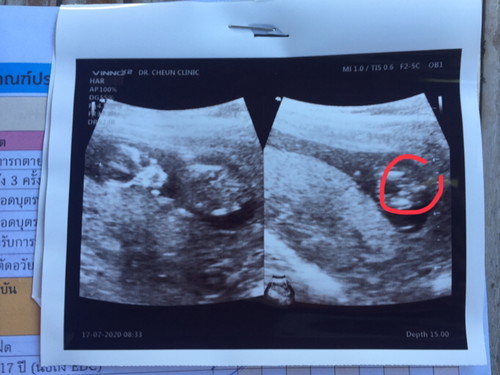

ช่วยดูหน่อยคะแม่ๆ หนูเด็กหญิง หรือเด็กชาย🥰 13W5D

ไม่เห็นค่ะแม่ ภาพไม่ชัด

ตรงสีแดงๆเป็นหว่างขาอะค่ะ